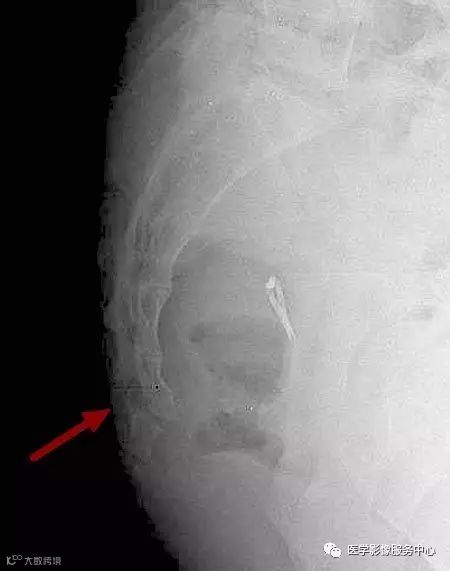

病人女性,外伤后骶尾部疼痛,dr片示骶尾关节对应关系差,骶5椎体欠规则。ct重建示骶5椎体粉碎性骨折!

X线